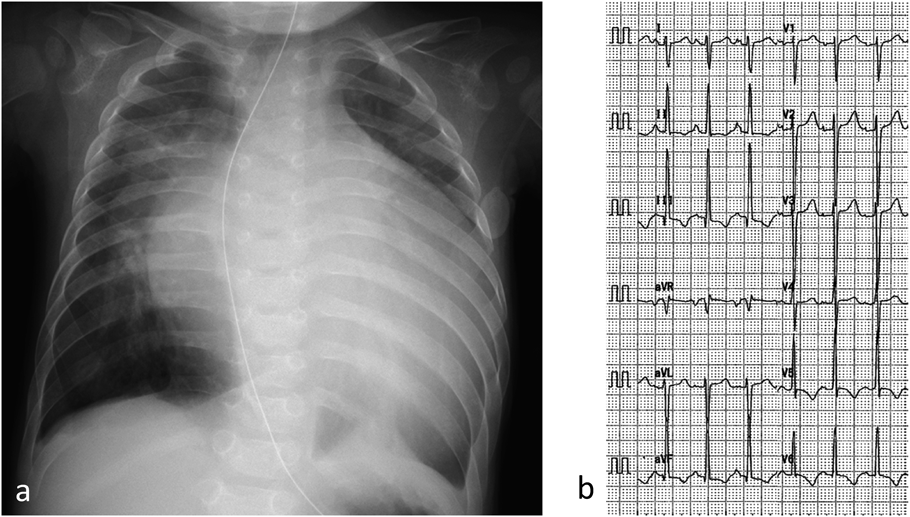

特発性拡張型心筋症に対し肺動脈絞扼術を施行した1乳児例Pulmonary Artery Banding in an Infant with Idiopathic Dilated Cardiomyopathy